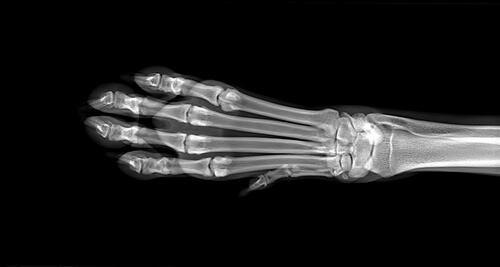

Para determinar la causa de la hinchazón, el veterinario hará una serie de pruebas diagnósticas entre las que destacan los análisis de sangre y orina, así como las radiografías de las extremidades. En el caso de que estas últimas no sean concluyentes, puede requerirse una resonancia magnética. Si hay sospecha de osteosarcoma, se realizará una biopsia de hueso.